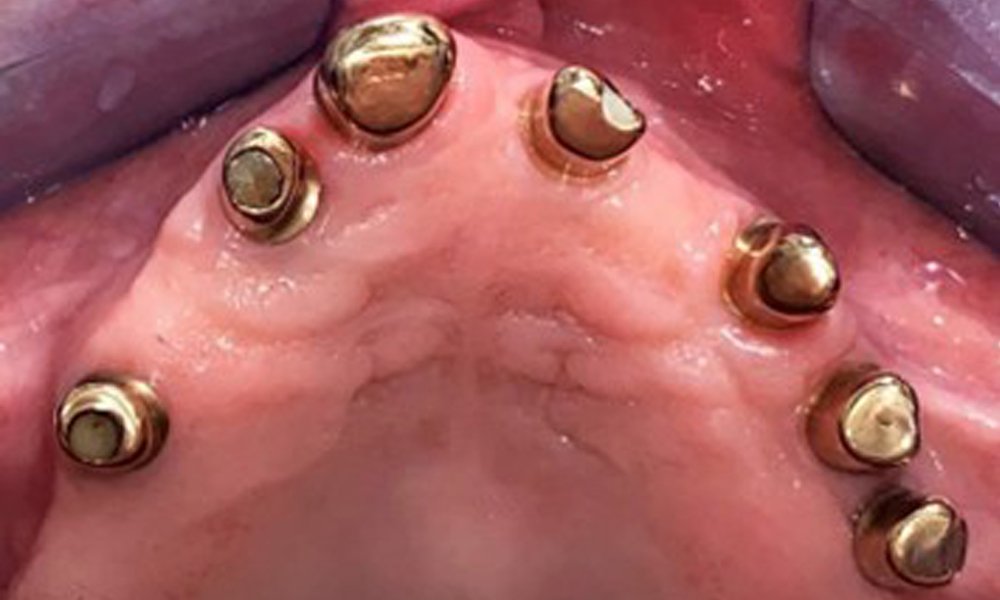

The patient was fitted with a combined removable maxillary telescopic prosthesis more than 25 years ago (Fig. 1, Fig. 2, Fig. 3) and is very happy with her dentures. The patient has an adequate fixed denture for the mandible (Fig. 4).

The dental findings are as follows: Combined removable implant and tooth-supported telescopic prostheses on implants 15, 13, 21, 23, 24, 25 and tooth 11 (Fig. 1, Fig. 2, Fig. 3). The patient was fitted with a fixed mandibular denture. Adequate bridges were present over 37 to 34 and 45 to 47 (Fig. 4), the crown margins were intact and there were no active caries. A composite filling with a marginal gap was present on tooth 43. There was mandibular gingival recession, exposing 1 to 3 mm of root surface. This also applies to 11.